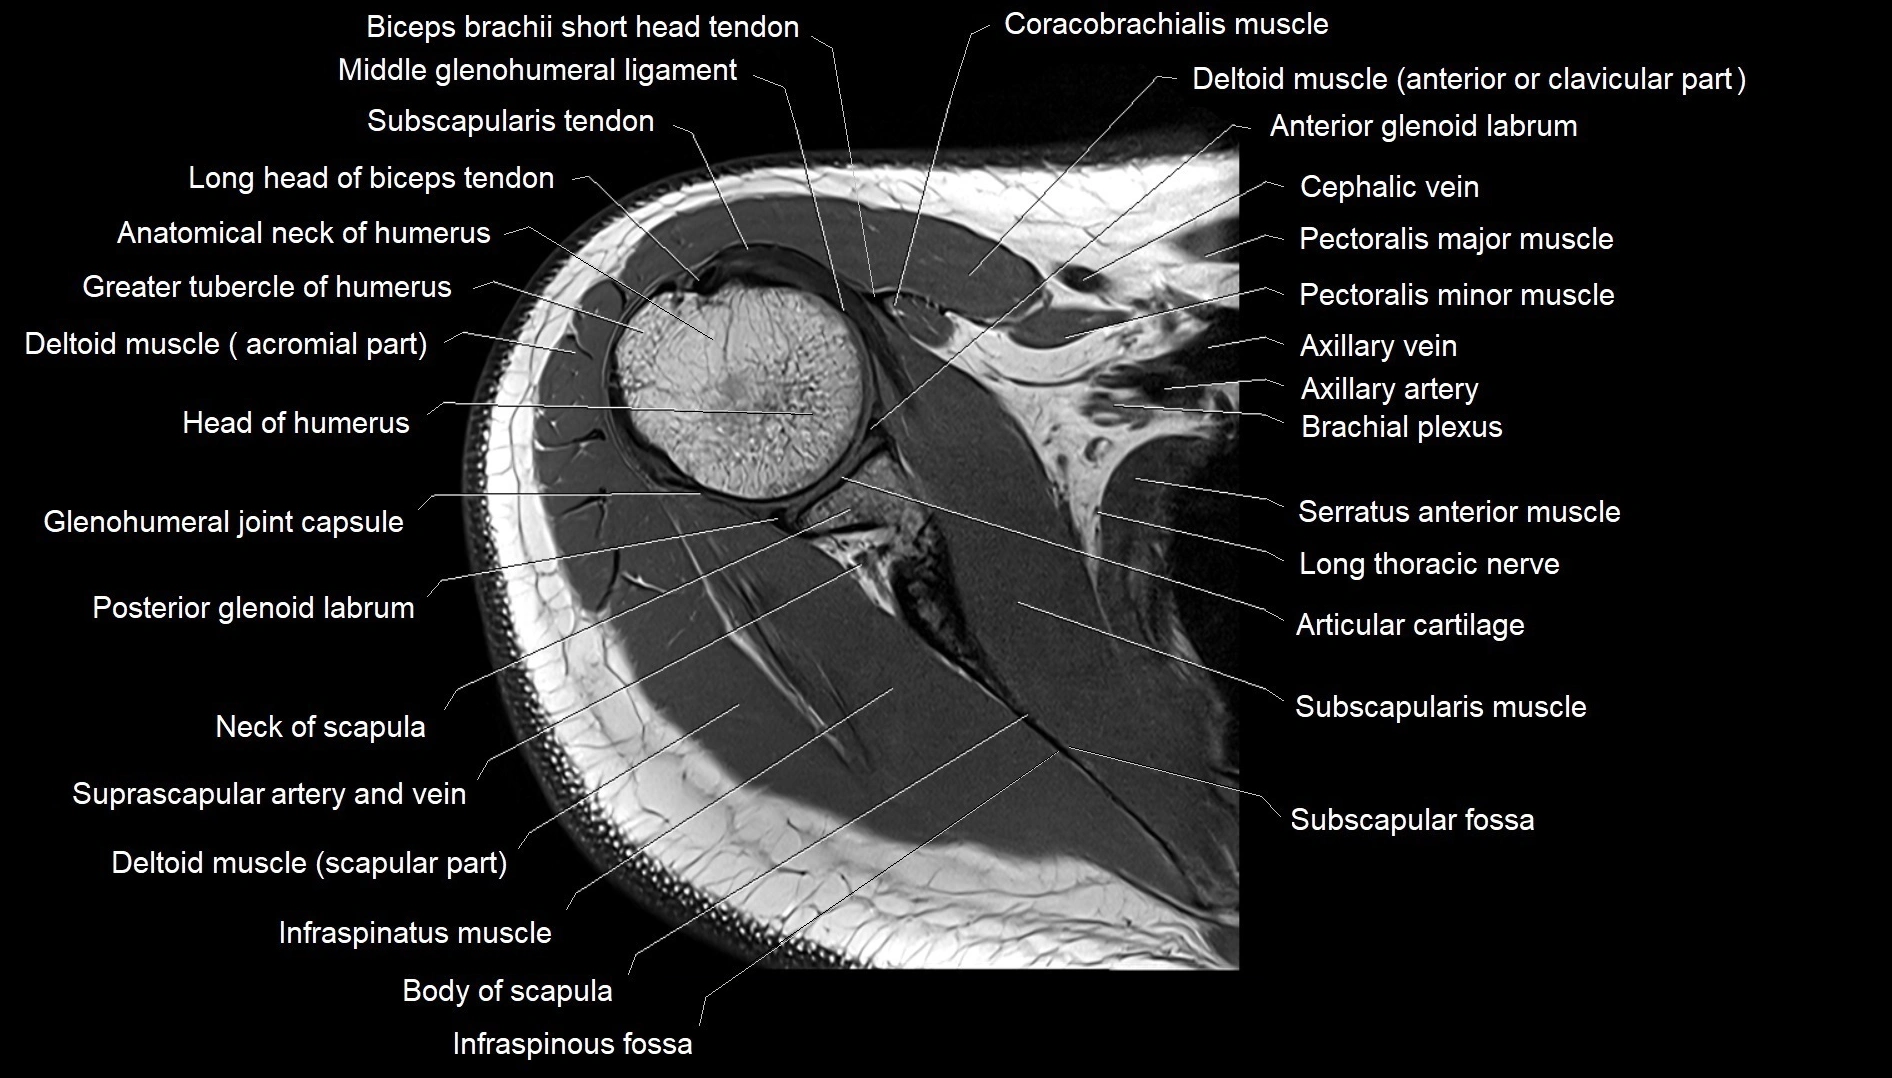

MRI images

image